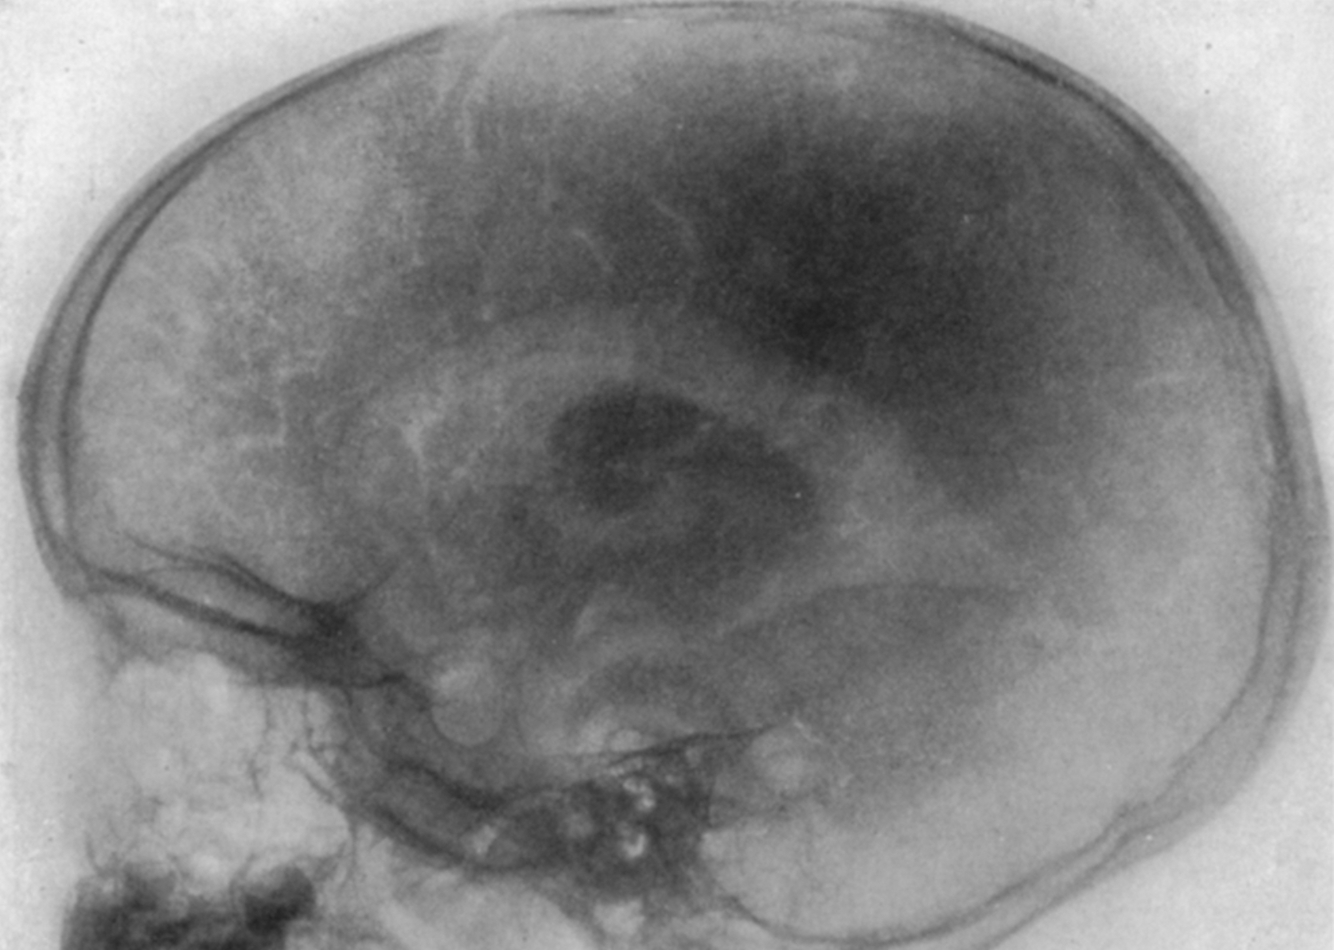

Wilhelm Rontgen

German Physicist, created first medical X-ray, Crookes tube X ray experiment.

Walter Dandy

Xrays to get medical diagnostics.

Ventriculography:

Ventriculography is a type of angiography in which x-rays are taken as a radiopaque contrast agent is injected into the left or right ventricle of the heart through a catheter. It is done during cardiac catheterization.

Pneumoencephalography:

A radiographic technique (now largely superseded) for examining the brain. It involved displacing the cerebrospinal fluid in the ventricles of the brain by air or oxygen, which served as a contrast medium

(-) Lack of X ray contrast within the skull.